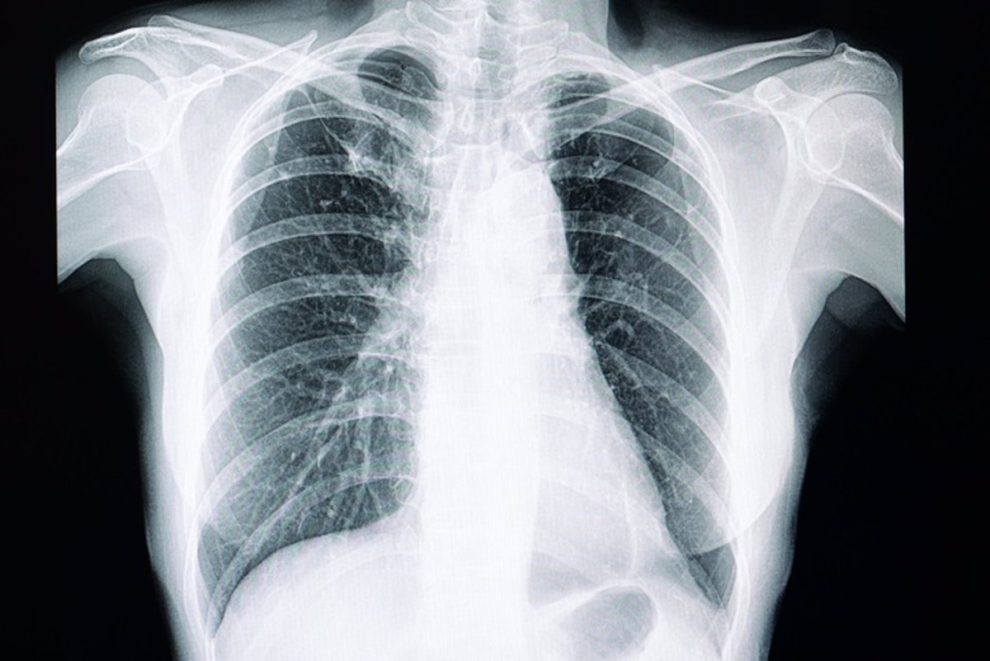

MADRID, 20 de marzo. (PRENSA UE) – Un estudio piloto del Instituto Americano de Física (EE. UU.) demuestra el mapeo sin contacto de las vibraciones superficiales del tórax durante la vocalización humana.

Más concretamente, un grupo de investigadores franceses demostró la eficacia de la tecnología de ultrasonido para detectar movimientos de baja amplitud generados por el sonido en la superficie del pecho. También demostraron la capacidad de utilizar la cámara de movimiento de superficie ultrasónica de aire (AUSMC) para mapear estas vibraciones durante cortos períodos de tiempo para ilustrar su evolución. AUSMC es una nueva tecnología de imágenes que permite observar vibraciones en la superficie del tórax humano debido a la actividad respiratoria y cardiovascular a altas velocidades de fotogramas, normalmente 1.000 fotogramas por segundo, comentó el autor Mathieu Couade.

Esta tecnología comparte los principios físicos de la ecografía Doppler convencional pero no requiere aplicar una sonda a la piel. Como se informa en ‘AIP Advances, de AIP Publishing’, los investigadores probaron AUSMC en 77 voluntarios sanos para obtener imágenes de vibraciones superficiales causadas por el habla natural en un intento de reproducir vibraciones vocales (vibraciones causadas por el canto en la superficie del cuerpo) como se analiza típicamente durante un examen físico del tórax. Informaron que se podían detectar vibraciones superficiales inducidas en todos los sujetos.

Couade enfatizó que se encontró que la distribución espacial de la energía vibratoria era asimétrica a favor del tamaño preciso de los senos y dependiente de la frecuencia en el eje anteroposterior. Como era de esperar, la distribución de las frecuencias de vocalización no se superpuso entre machos y hembras, siendo estas últimas más altas. Los ensayos clínicos en curso utilizarán AUSMC para centrarse en identificar patologías pulmonares.

Pero los investigadores esperan que esta tecnología, junto con los algoritmos de inteligencia artificial, pueda marcar el comienzo de una nueva era en los exámenes mamarios en la que se puedan aislar patrones de vibración. Esto proporcionará una mejor visión de la salud respiratoria y permitirá un mejor diagnóstico de las enfermedades respiratorias.